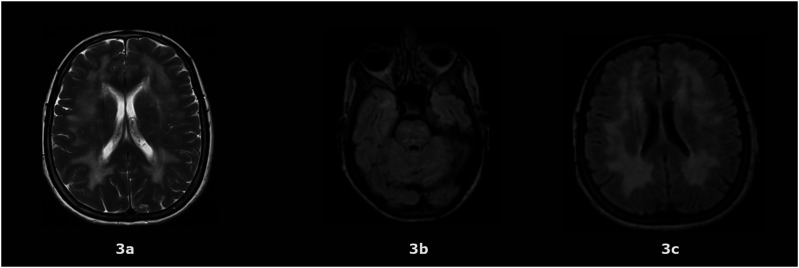

Abstract Image